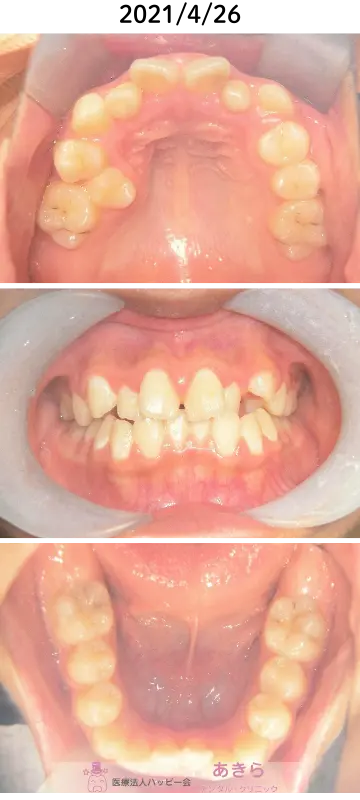

2021年4月26日 初診時口腔内写真

右上5番の著しい口蓋側転移位を伴なうケース

上顎左右1番捻転

上顎右側2番舌側転位

右上5番口蓋側転位

上下右側2番クロスバイト

上下顎叢生

上顎左右2番矮小歯

上下顎狭窄歯列

歯牙脱灰著名